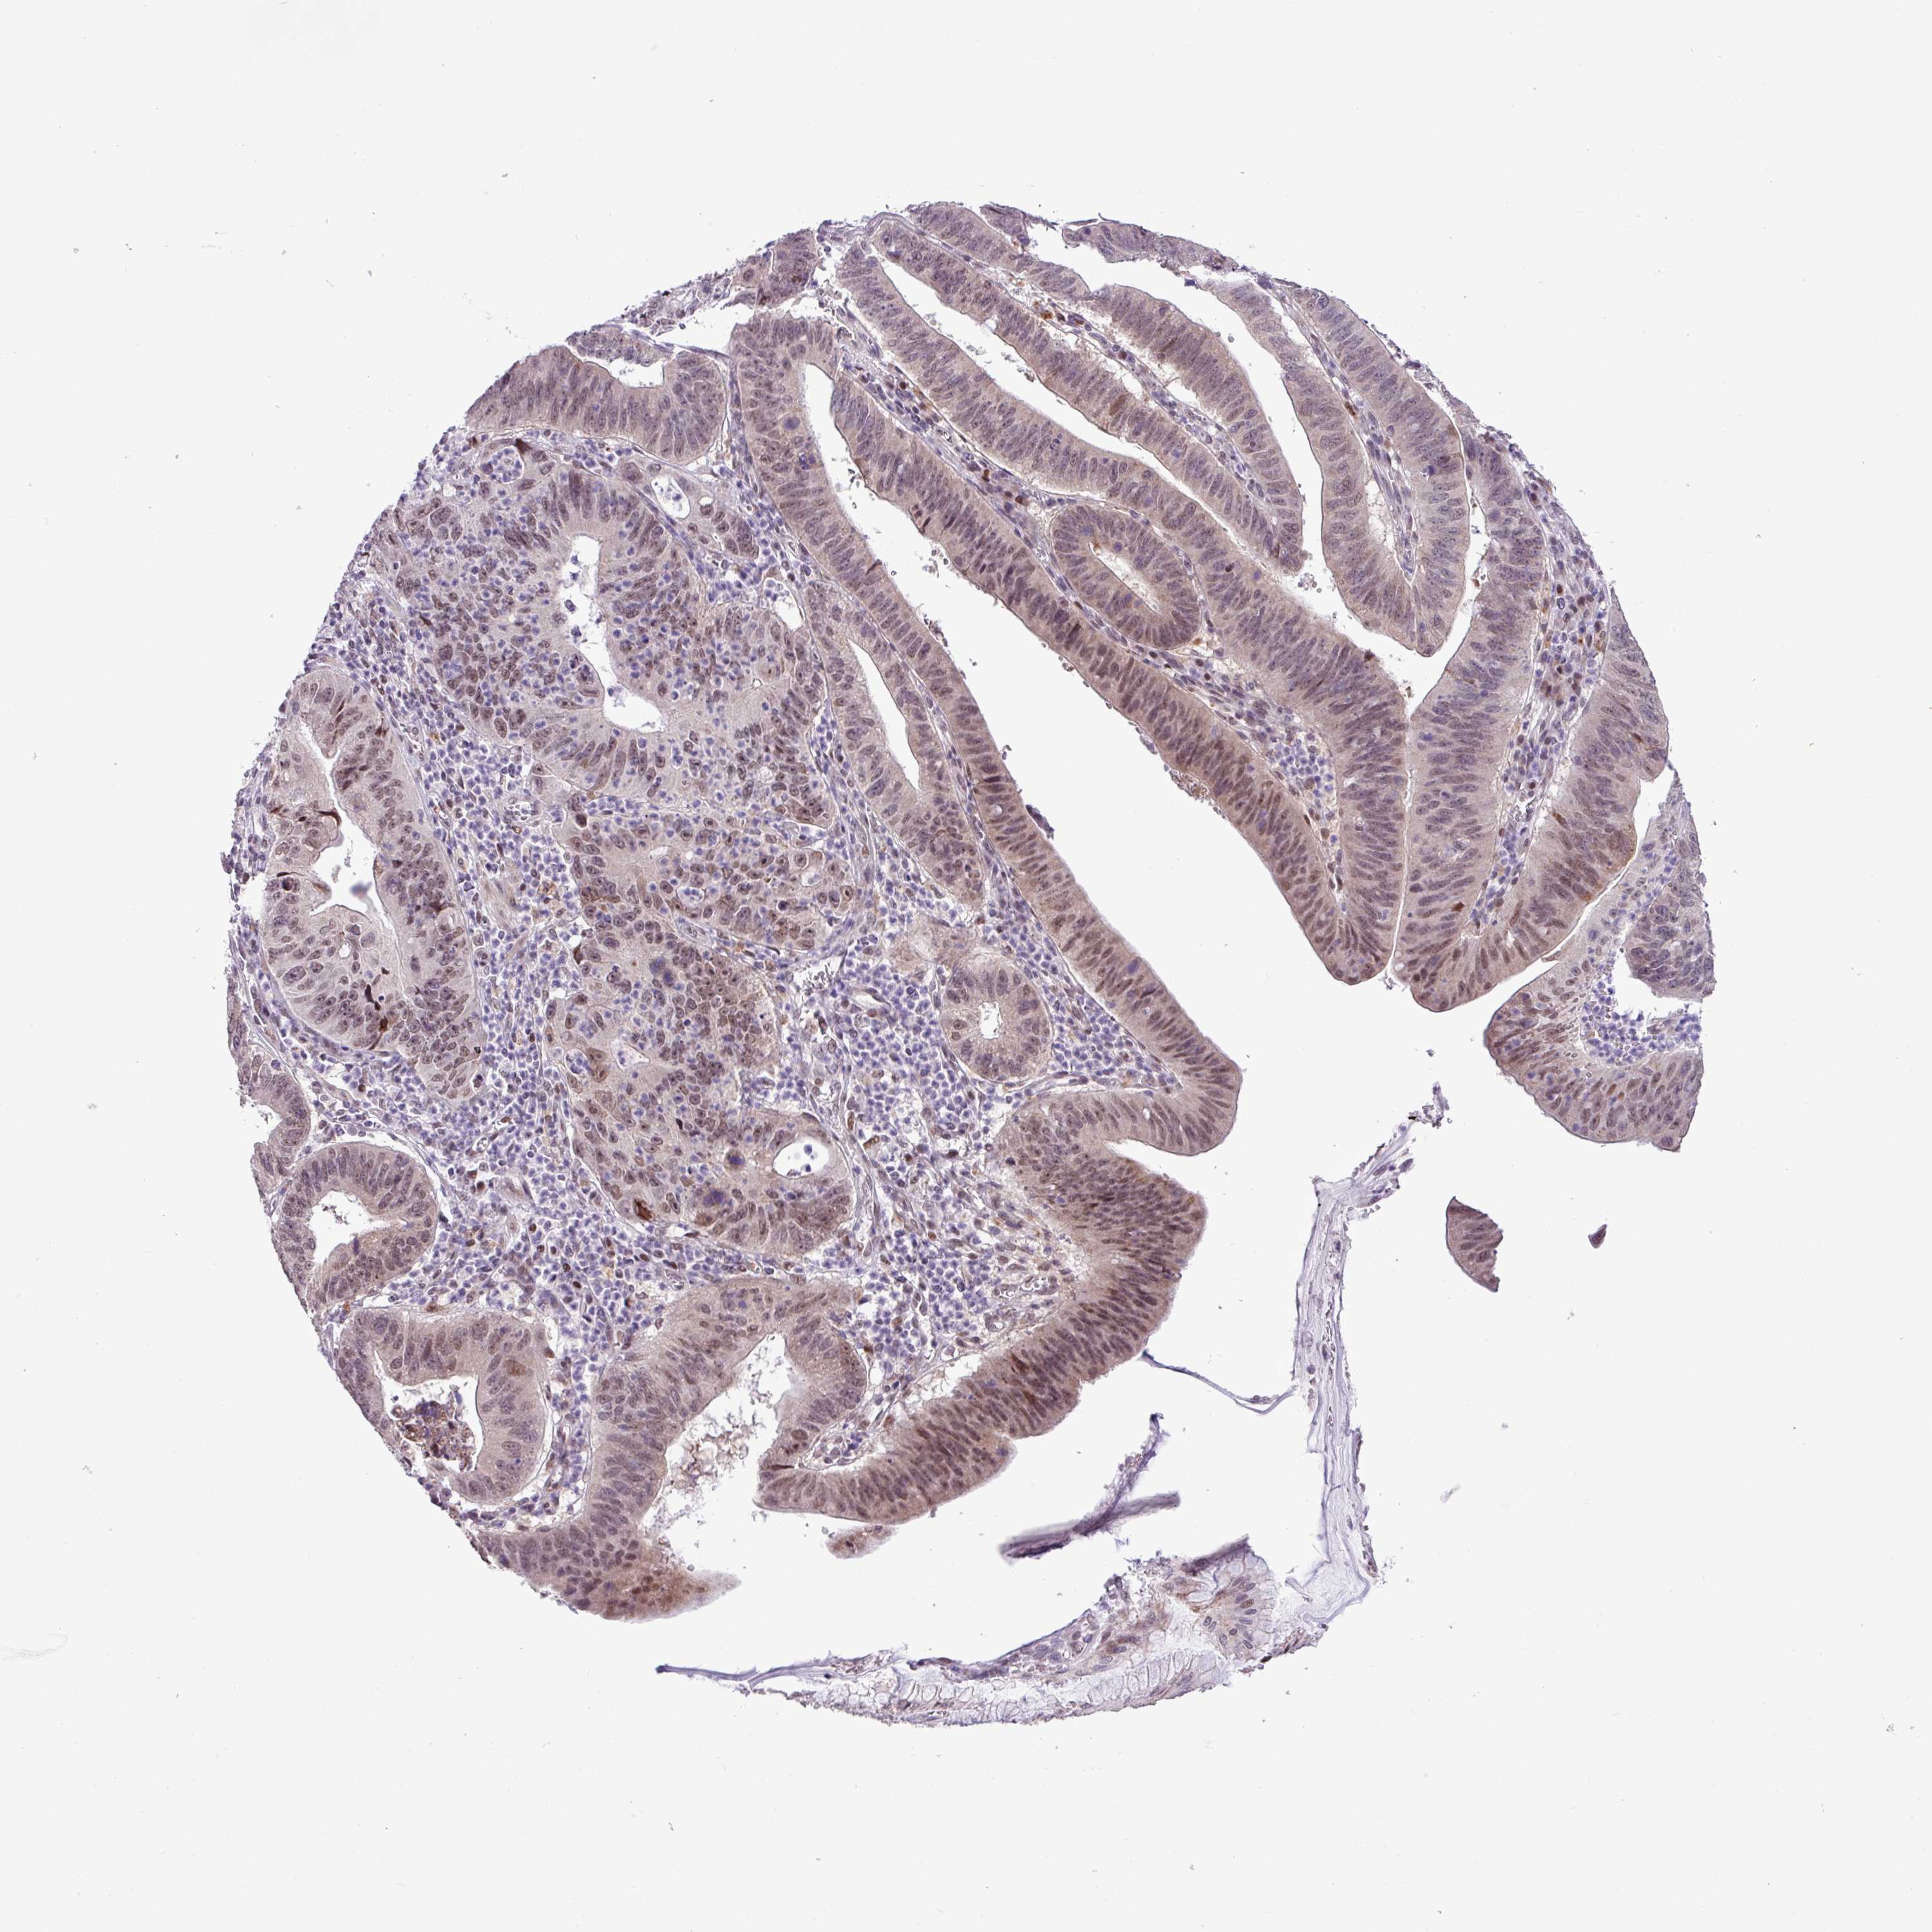

STOMACH CANCER - Protein expressioni

A mouse-over function shows sample information and annotation data. Click on an image to view it in a full screen mode. Samples can be filtered based on level of antibody staining by selecting one or several of the following categories: high, medium, low and not detected. The assay and annotation is described here.

Note that samples used for immunohistochemistry by the Human Protein Atlas do not correspond to samples in the TCGA dataset.

Antibody stainingi

Antibody staining in the annotated cell types in the current human tissue is reported as not detected, low, medium, or high, based on conventional immunohistochemistry profiling in selected tissues. This score is based on the combination of the staining intensity and fraction of stained cells.

Each image is clickable and will lead to virtual microscopy that enables deeper exploration of all samples and also displays staining intensity scores, fraction scores and subcellular localization as well as patient and tissue information for each sample.

Antibody HPA052043

Staining

High

Medium

Low

Not detected

Intensity

Strong

Moderate

Weak

Negative

Quantity

>75%

75%-25%

<25%

None

Location

Nuclear

Cytoplasmic/membranous

Cytoplasmic/membranous,nuclear

Adenocarcinoma, NOS